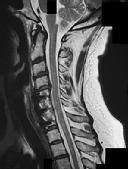

Preoperative MRI images are shown from a 67-year-old woman with neck pain, bilateral upper extremity paresthesias, progressively worsening balance, several falls, and increasing problems in both hands with dropping objects. Figure 1 is a sagittal view, Figure 2 is an axial cut at C2-3, Figure 3 is an axial cut at C5-6, and Figure 4 is an axial cut at C6-7. The patient’s motor strength is grade 4+ of 5 in the bilateral upper extremities.

The patient has degenerative changes with central and foraminal stenosis from C2-7, including spinal cord compression at C2-3, C5-6, and C6-7. Her progressively worsening balance, falls, and clumsiness are consistent with cervical spondylotic myelopathy. Given the progressive nature of the neurologic symptoms, surgery is recommended for patients with worsening

symptoms. Physical therapy potentially could provide pain relief but would not address the spinal cord compression. Cervical epidural steroid injection is not recommended because of the increased neurologic risk in the setting of substantial spinal cord compression. Given the multiple levels involved and the extension to the C2-3 level, an anterior approach would increase the risk of morbidity and pseudarthrosis compared with the posterior approach, which would allow adequate decompression of the central and foraminal stenosis.

Surgery for cervical myelopathy is performed to decompress the spinal cord, stabilize the spine, and prevent further neurologic injury. Most patients obtain considerable pain relief and some improvement in balance and clumsiness, depending on the severity of the symptoms. Complete resolution of all symptoms should not be expected.